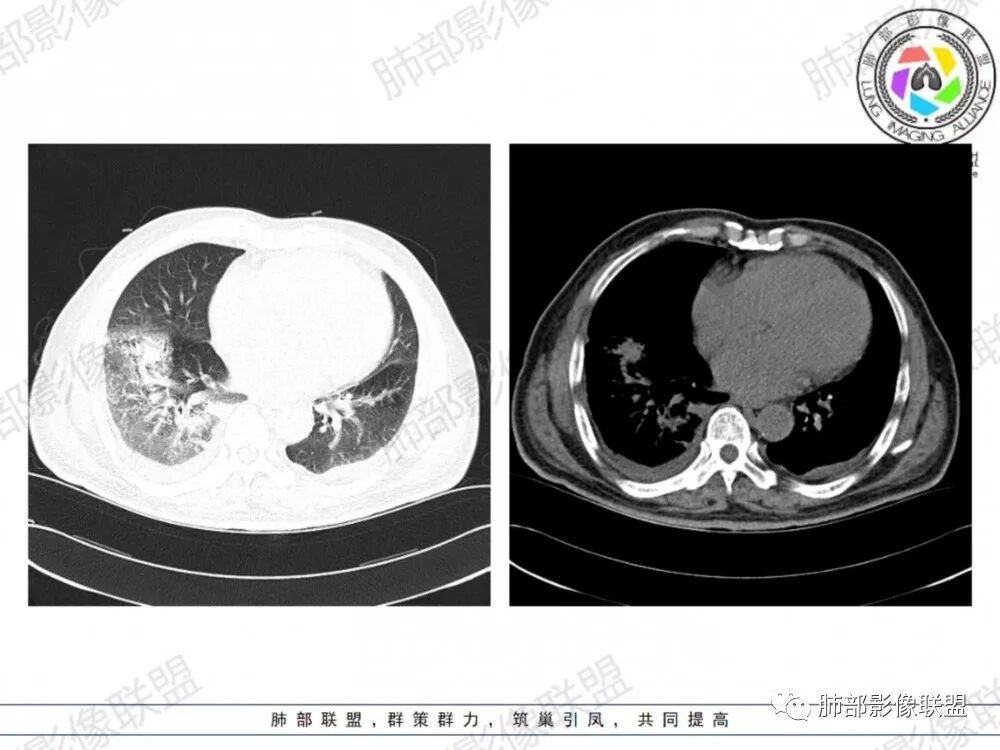

晨读:老年男性患者,咳嗽气喘3天入院,伴有发热,体温38.2℃,有糖尿病,高血压病史,有长期吸烟史,近期旅游史,白细胞,中性粒,CRP,PCT增高,肝功能损害,血气分析:低氧血症,胸部CT:双上肺及右下肺实变密度影伴周围磨玻璃密度影,边界整体清楚,内部支气管走形自然,伴双侧少量胸腔积液,综合考虑感染性病变,重症社区获得性肺炎,重点考虑非典型病原体,军团菌可能,鉴别肺克,结核合并感染

晨读老年患者,咳嗽气喘三天,腹泻,有多脏器的损害。有基础病的病史,糖尿病,高血压。旅游病史。两位靠后分布的大片状的实变影及磨玻璃样阴影,跨叶小叶性的分布,支气管充气征。内部的小叶间隔局部增厚。纵隔淋巴结不大,右侧胸腔积液。首先考虑感染性的病变,靠后重力感,肺克雷伯杆菌肺炎。鉴别诊断军团菌肺炎。

双肺多发斑片及大片状高密度影,周围伴磨玻璃影,界欠清晰,内见多发囊状透亮影呈蜂窝状,病变内支气管走形规则,无肺气肿背景,双侧胸腔积液,老年男性,糖尿病史,消化道症状,炎性指标升高,考虑军团菌感染,克雷白杆菌感染待排。

双肺大片磨玻璃影伴实变,边缘清晰,支气管通畅,磨玻璃影部分呈细网格状,胸膜下清晰,双侧胸腔积液,心影增大,心腔密度减低,贫血,考虑肺克,军团菌

胸部CT示双肺弥漫实变影伴周围磨玻璃影,跨叶段分布,可见小叶间隔增厚,支气管充气征,双侧胸腔积液。无明显坏死空洞及树芽征。

CT:双肺多叶段毛玻璃影、实变影、小叶内间质增粗,肺内病变有重力依赖趋势,双侧少量胸腔积液,无空洞、树丫;

军团菌感染可累及多个脏器,肺是主要的受侵器官。军团菌肺炎为广泛多叶分布的炎症。

1.病变复杂多样∶大片状实变影、斑片状模糊阴性,网格状阴性、小结节影。多叶受侵是本病重要影像学特征性改变。

3.呈小叶肺炎状改变,病变大小以肺小叶为单位的支气管肺炎,呈弥漫性的单或双侧分布。局部可融合呈高密度的团片状影像,本病又一典型的影像学特点。

4.病变常伴有胸水出现,肺部阴性多变的情况下伴有胸水形成应高度怀疑军团菌感染的可能。